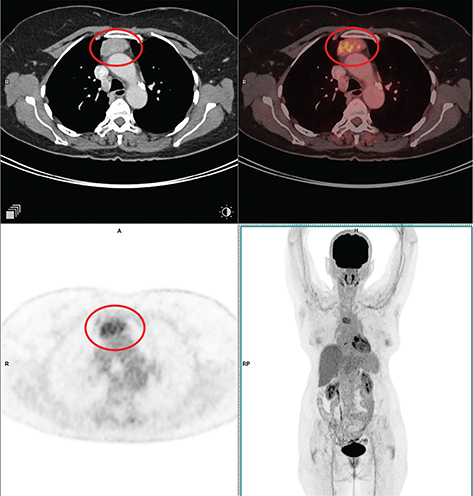

Fig 1

Figure 1. Type A thymoma. Anterior mediastinal mass that was pathologically confirmed as type A thymoma. FDG PET/CT images include axial CT (top left panel), fused axial PET/CT (top right panel), axial PET (bottom left panel), and maximum intensity projection (MIP) PET image (bottom right panel). In the red circle, there is a soft tissue density mass with well-defined contour showing homogenous enhancement in CT with moderate FDG uptake on PET. No evidence of infiltration of adjacent structures. No other metabolically active disease in the whole-body survey.